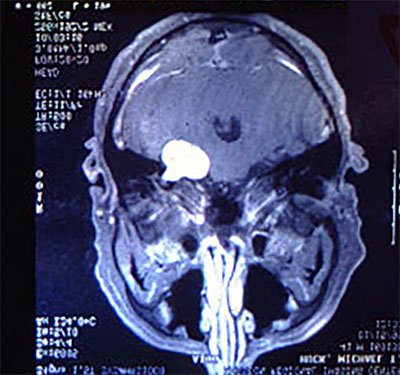

Surgery 19 years ago to remove a benign tumor the size of a golf ball that was pushing against his brain and a cluster of nerves has left the 61-year-old Huck essentially with one good ear and a positive outlook that can inspire others.

It wasn't until Huck sought help from an ear, nose and throat specialist that he learned neither his hobby nor his job was to blame. An MRI revealed a tumor, called an acoustic neuroma, the size of a golf ball in his inner ear.

It wasn't until after the tumor was removed that the surgeon could perform a biopsy that showed the growth was benign. That was the good news. The bad news was that in the meantime, it had crushed the acoustic nerve, resulting in a 90-percent hearing loss in his right ear.

"The problem wasn't that it was cancerous; it wasn't.The problem was space occupation and location," he said. "It was wedged against the brainstem and where the spinal cord and nerves come together. If it were allowed to grow, it could crush a nerve that controls involuntary functions, like breathing. Then you fall over and they think you've just had a heart attack."